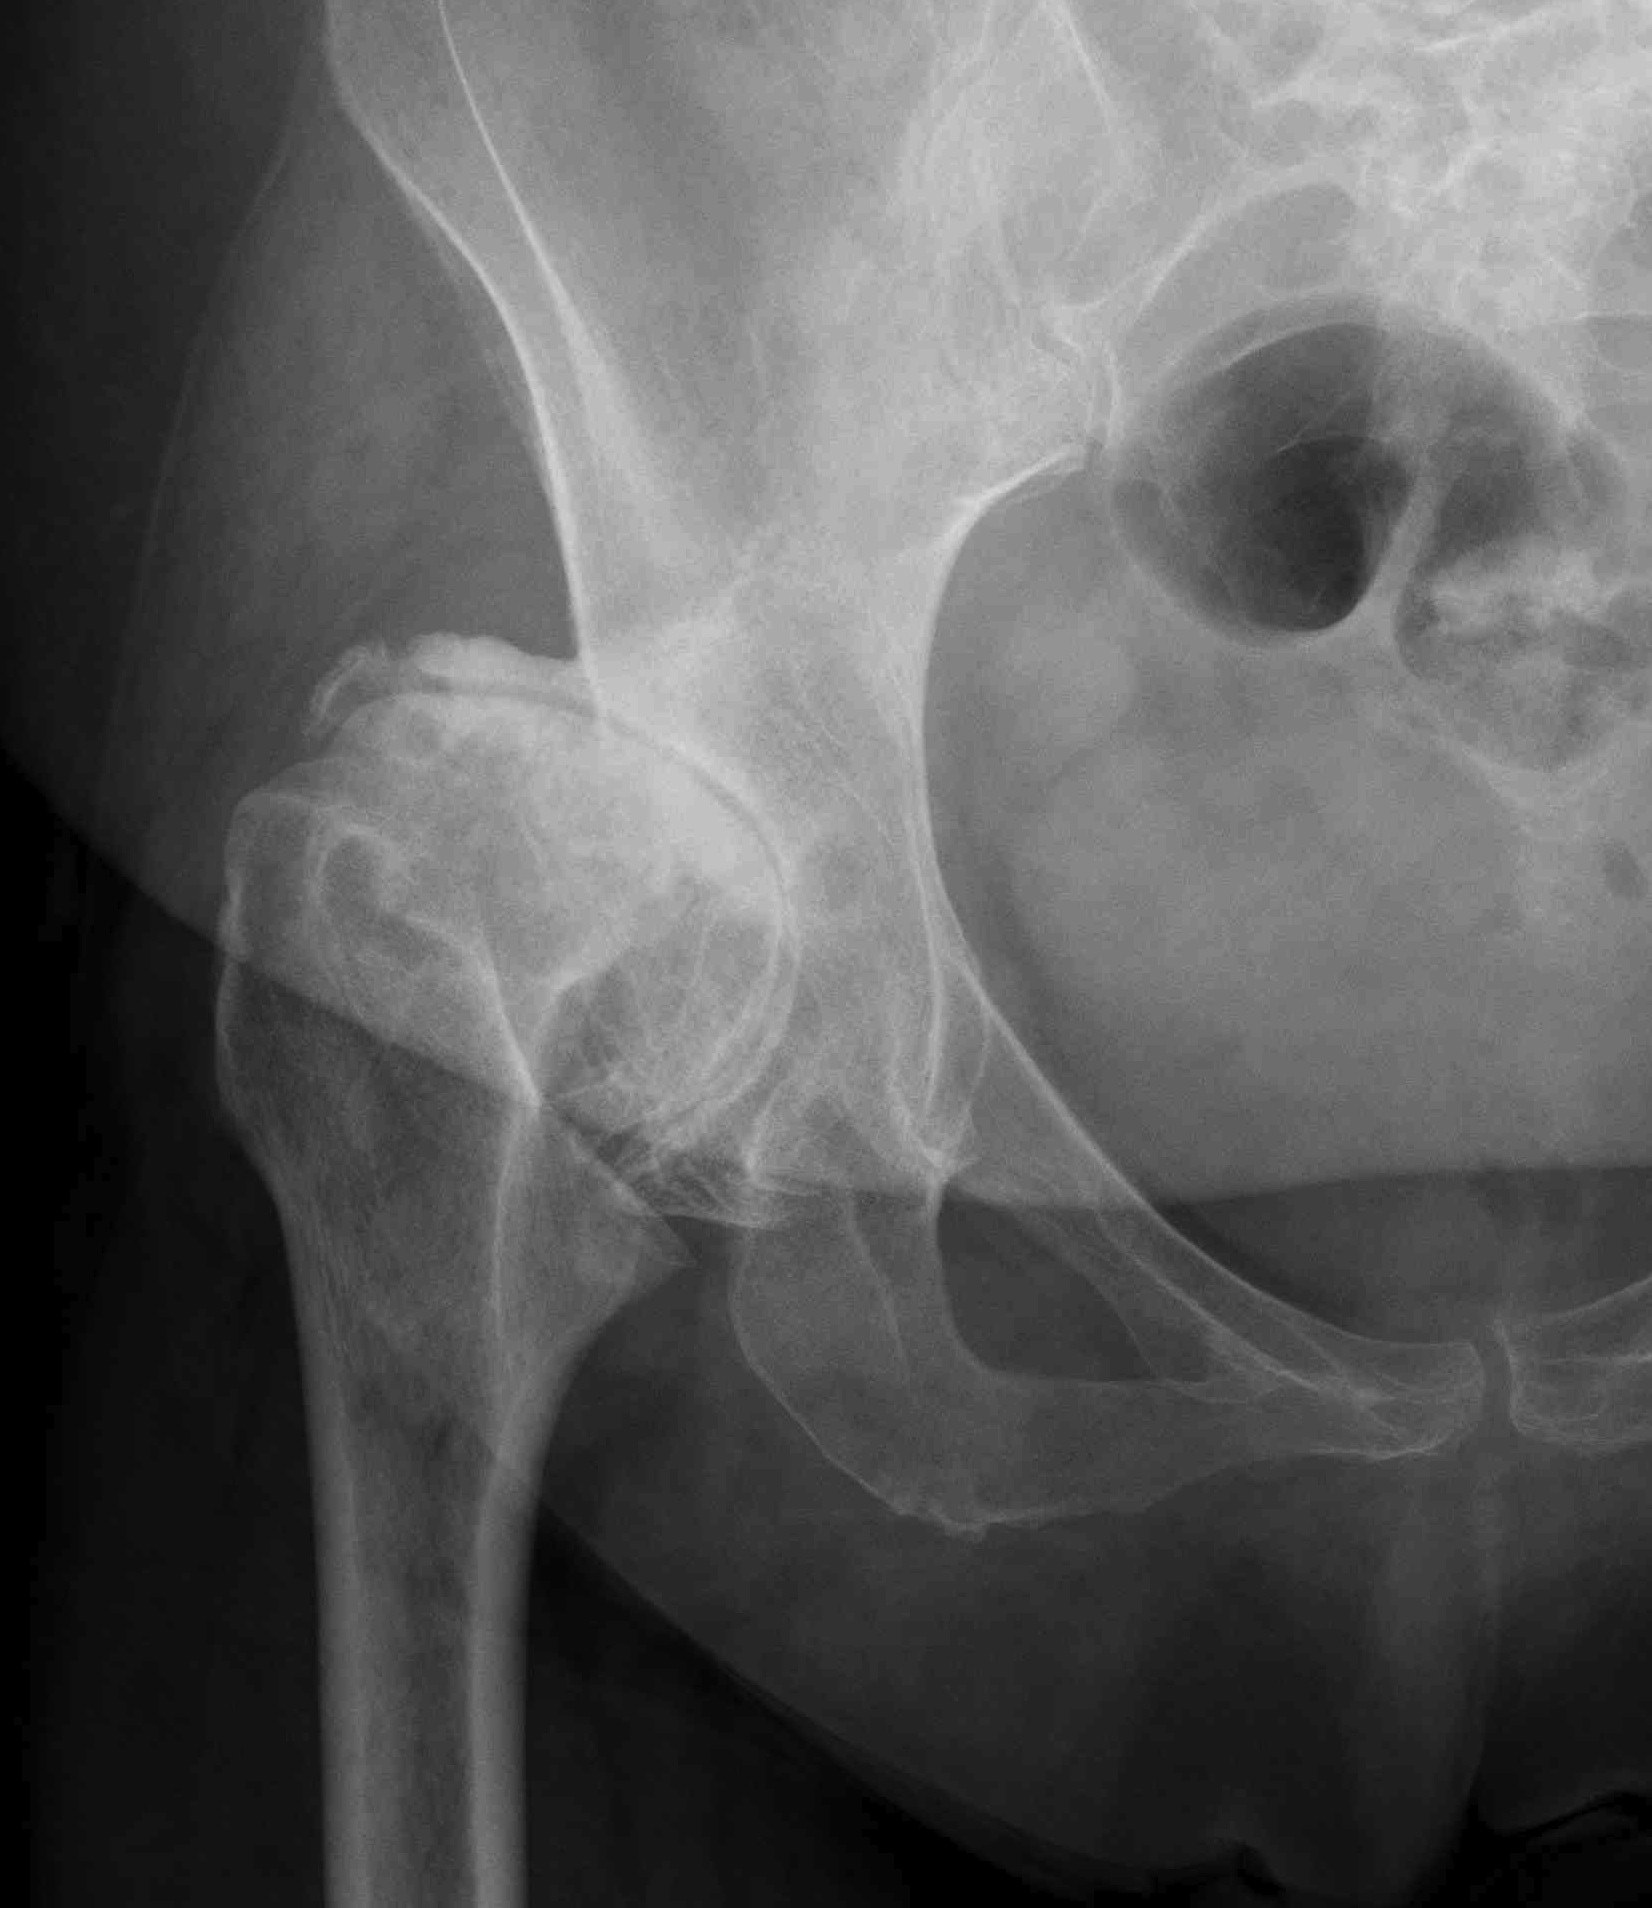

Crowe I

Crowe II

Crowe III

Crowe IV